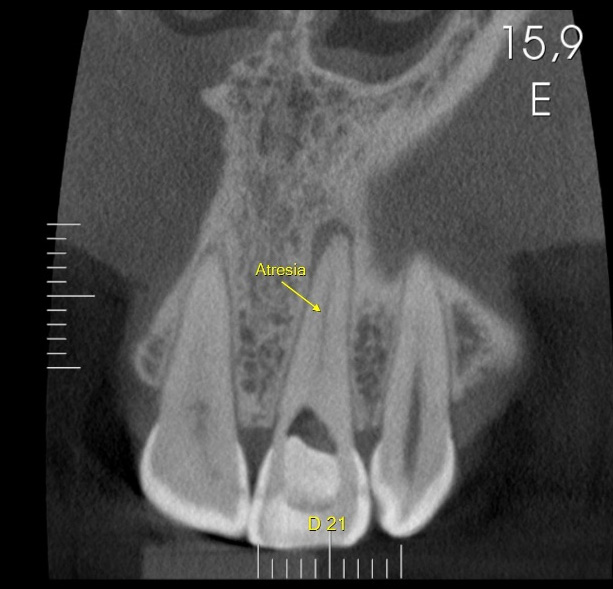

Tooth #11 with a calcified canal following traumatic injury